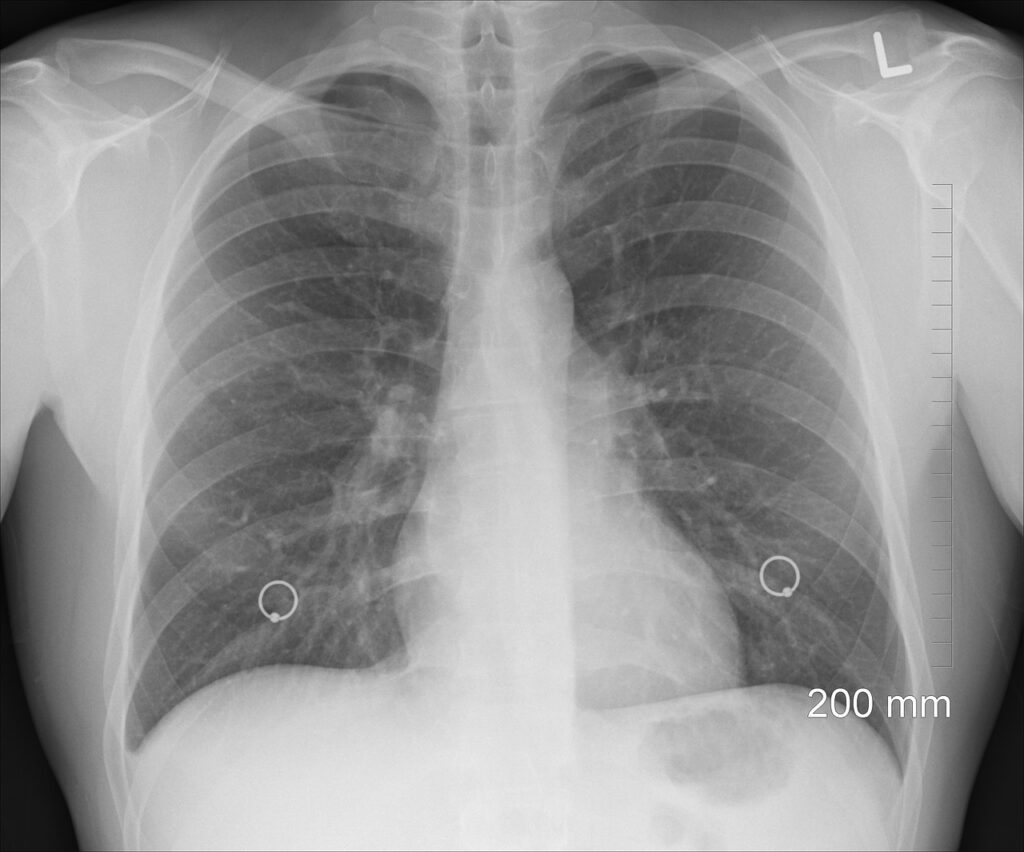

„Svi naši sugrađani, stariji od 50 godina, koji imaju pušački staž duži od 30 godina, su ciljana populacija, odnosno ključne osobe za ovaj skrining. Njima će biti urađen CT pregled za skrining karcinoma pluća, koji se radi po niskodoznom protokolu“, naveo je ministar. Rekao je i da na svaka dva sata jedna osoba premine od raka pluća.